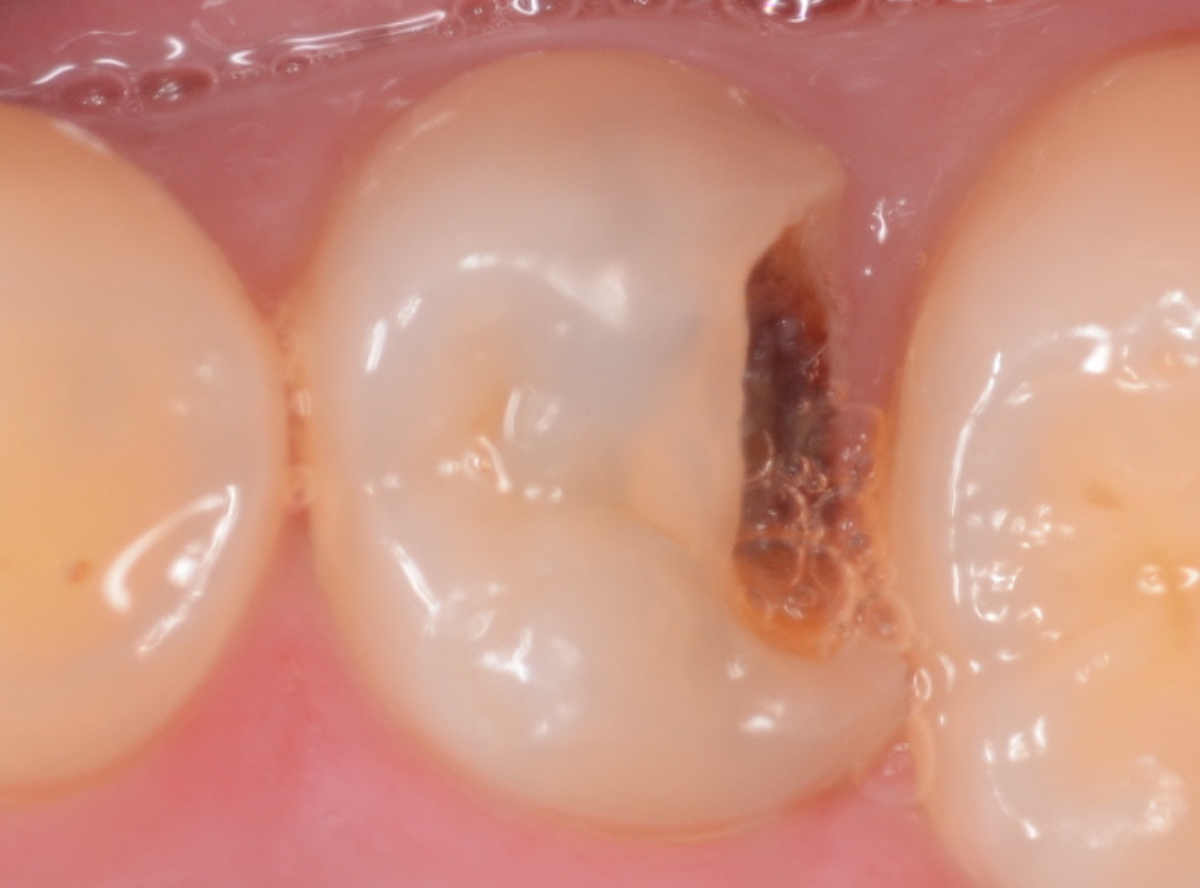

虫歯を取り残さないための「う蝕検知液」

虫歯を取り残してしまう原因は何でしょうか?

それは虫歯が一目見ただけではわからないからです。

黒くても削らなくていい場合もあります。黒くなくても削らなければいけない場合もあります。

う蝕検知液とは、虫歯の部分のみを赤く染める薬剤です。

写真は、虫歯治療をしている途中の写真です。どこに虫歯があるかわかりますか?

赤く染まった部分が虫歯です。

そして、虫歯を取り切った写真を見るとかなり大きな虫歯であった事がわかります。

虫歯治療を行う上で一番大切な事は、虫歯に感染した部分をしっかり除去することですが、まずは虫歯の硬さを頼りに、軟らかくなった部分を削っていきます。

「虫歯の部分だけを削るドリル」を使用すれば、それだけでほぼ虫歯は取り除けますが、感染部位を完全に除去できたかわかりづらい時もあります。

このう蝕検知液を併用することで、虫歯を取り残すことなく虫歯治療ができます。

う蝕検知液で細かくチェックする事で、虫歯治療の精度があがります。